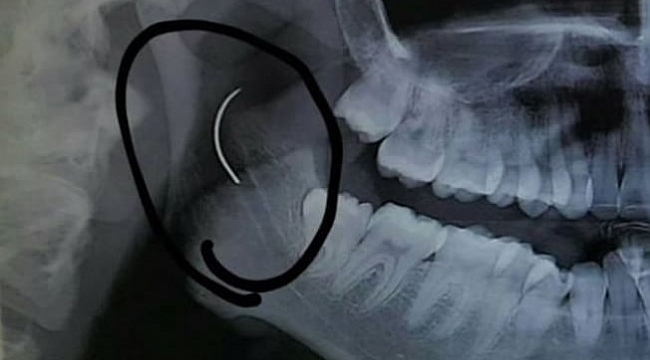

Boğazındaki iğneyle geçen 18 yılını anlatan Meltem Cansız, "3 yaşında geçirdiğim bademcik ameliyatında iğne boğazımda unutulmuş. Daha sonra iğneden dolayı 11 yıl sonra 14 yaşındayken kulak rahatsızlığım ortaya çıktı. Kafamın sağ tarafı ağrımaya başladı. Doktora gittik, hiçbir şey olmadığını söylediler. Sonrasında beni MR çekilmek üzere Akhisar'a yönlendirdi. Gecenin bir vakti MR'a girdim. Ancak bir türlü çekemediler. Benim üzerimde toka vs. metal bir şey olduğunu söylediler baktılar ancak bir şey yoktu. Üç yada dört defa MR'a girdim. Ancak bir türlü çekemediler. Sonra doktorumuz röntgene yönlendirdi. Röntgen görüntüsünde ameliyattan kalma bir çengelli iğnenin boğazımda olduğu görüldü. Bunun için beni Ege Üniversitesi'ne sevk ettiler. Burada doktorlar bu ameliyatı yapabileceklerini ancak riskinin çok olduğunu söylediler. Biz yine de kabul ettik. 1,5 saatlik operasyon geçirdim ancak iğneyi bulmadıklarını söylediler. 2 sene kadar araştırma yaptık. Birçok hastaneyle görüştük. Ancak ayağımda bir rahatsızlık meydana geldi. Ayağım için Ege Üniversitesi'ne gittik. Tekrardan beni ameliyat eden doktorumla görüştüm. 'Seni ben ameliyat ettim, tekrardan buna kalkışamam' dedi. MR'a da giremezsin dediler. 'Sen bununla yaşamayı öğren' en azından bunun için çabalama alınmaması daha iyi dediler. Ben daha genç bir kızım sonuçla bu iğneyle ömür boyu yaşayamazdım. Yaşanan bu olumsuzların ardından araştırmalarımız neticesinde en son İzmir'de özel bir hastaneye gittik. Oradaki doktorum Çağlar Çallı bey bana umut verdi. 'Bu iğneyi alacağız' dedi. İnancımı kaybetmedim, sonucun ne olacağını bilmeden girdim ben o ameliyata. Ölüm, felç olma riskim çok fazlaydı. 'Yaşayamayabilirsin' dediler, biz bile bile lades dedik. Sonucu da güzel oldu" dedi.

Ege Üniversitesi'ne gittiklerini belirten baba Cansız, iğnenin şah damarına çok yakın olduğunun söylendiğini belirterek şunları söyledi: "Doktorlar çok tehlikeli bir ameliyat olacağını yanlış ya da en ufak bir hatada kızımızın bir tarafının felç kalabileceğini veya hayatını kaybedebileceğini söylediler. Biz bu riski göze alarak ameliyata müsaade ettik. Fakat iğneyi görüldüğü yerde bulamadıklarını söyleyerek alamadılar. Sonra İzmir Çiğli'de özel bir hastanede denedik. Kendisine binlerce kez teşekkür. Allah razı olsun. Çocuğumun boğazındaki iğneyi aldı. Dünyalar bizim oldu."